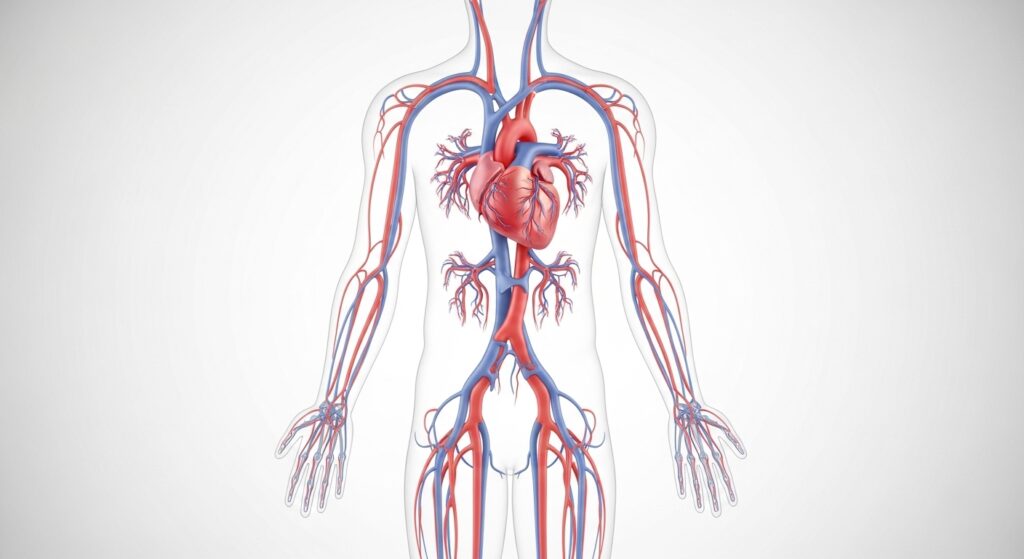

Circulation plays a central role in how the male body maintains daily energy and overall vitality. Proper blood flow allows oxygen and essential nutrients to reach tissues efficiently, supporting physical performance and recovery. This process is influenced by multiple factors, including diet, activity level, and nutrient availability.

Nutrients such as certain plant compounds, minerals, and amino acids are commonly studied for their role in supporting circulation-related processes. When combined with balanced habits, these nutrients may help maintain the body’s natural systems over time.